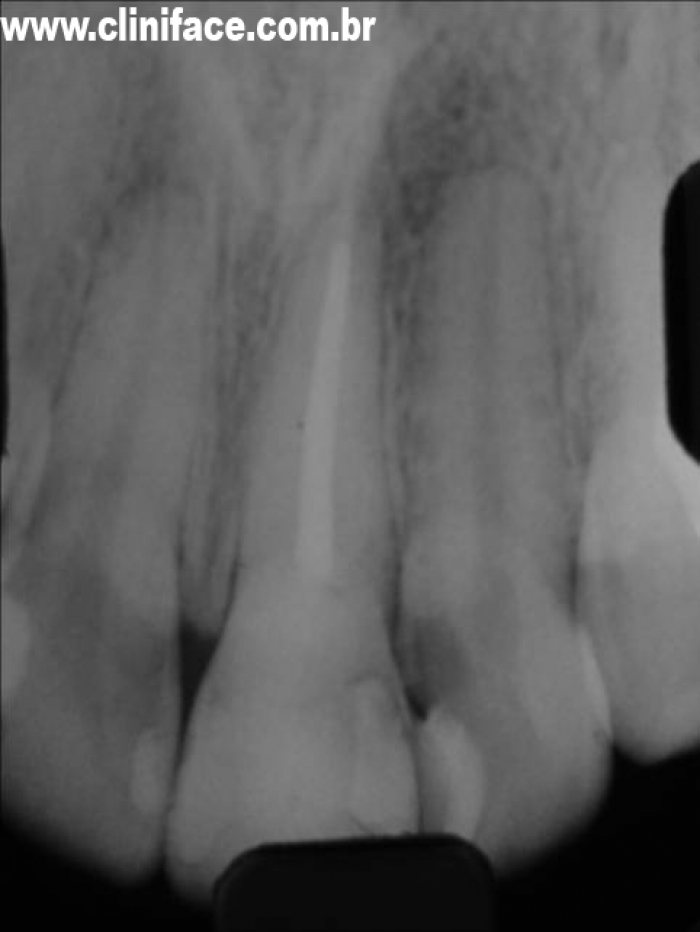

Raio X inicial do dente 21 fraturado